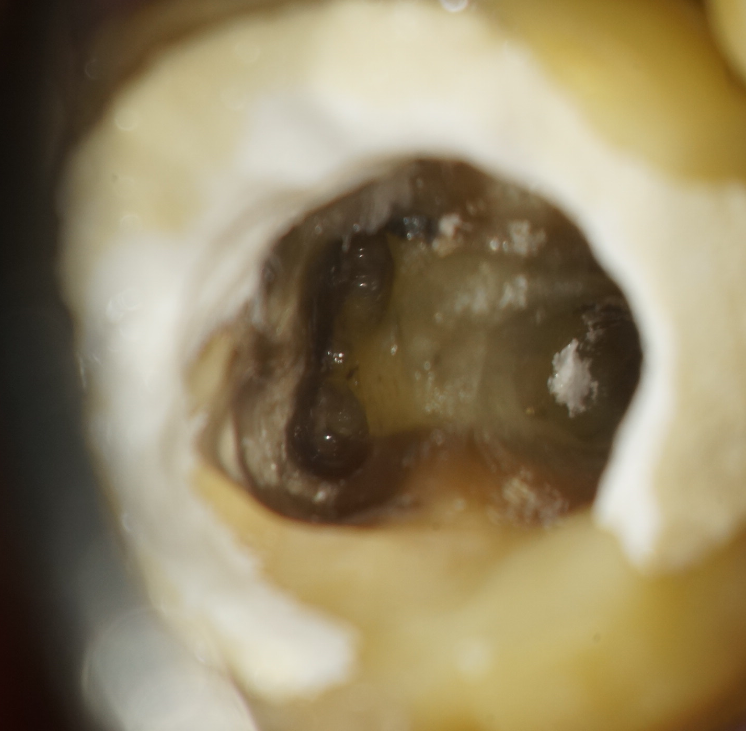

実際に診に見えないところを、レントゲンを参考に想像しながら、経験と勘で治療していたといっても過言ではありません。 しかしマイクロスコープ(顕微鏡)を使うと確実に肉眼で見ながら治療できるようになり、とても精度の高い、成功率の高い歯科治療ができるようになります。

マイクロスコープ(顕微鏡)治療は特に、根の治療(根管治療)や歯根端切除、修復・充填、かぶせ(インレー・クラウン・ブリッジ)、抜歯等において私には欠かせない右腕となっています。